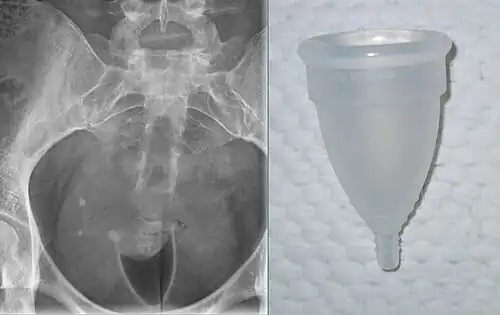

An X-ray that shows a bell-shaped menstrual cup in place. The cervix can be seen in the mouth of the cup; the cup rim is in the vaginal fornix. Bell-shaped cups have the same shape when in use inside the body as outside, and create an empty space (black on the X-ray).

An X-ray that shows a bell-shaped menstrual cup in place. The cervix can be seen in the mouth of the cup; the cup rim is in the vaginal fornix. Bell-shaped cups have the same shape when in use inside the body as outside, and create an empty space (black on the X-ray). -

An MRI showing a bell-shaped menstrual cup in place; cup in blue, uterus in red. The ectocervix (the portion of the cervix that protrudes into the vagina) sits inside the cup. Sagittal plane.

An MRI showing a bell-shaped menstrual cup in place; cup in blue, uterus in red. The ectocervix (the portion of the cervix that protrudes into the vagina) sits inside the cup. Sagittal plane.

While many diagrams show bell-shaped menstrual cups very low in the vagina, with the vagina gaping open, in-vivo imaging shows that the cups sit high, with their rim around the cervix, and the vagina squishes shut below the cup, sealing it inside the body.[7]